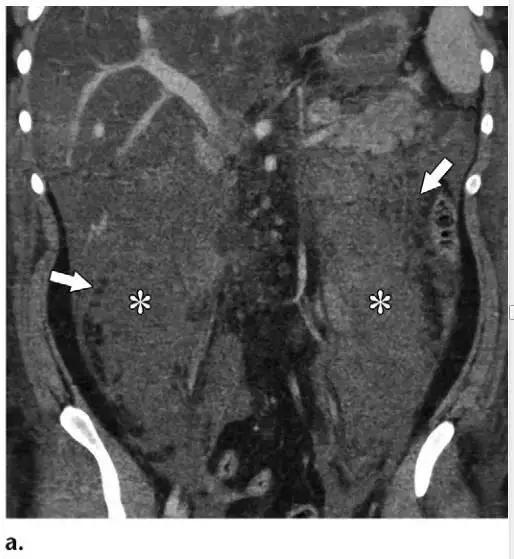

同时受累的亚型:表现为胰腺及胰周无强化坏死物,多累及小网膜囊和肾前间隙(图 3a)。

胰周型:表现为胰腺强化正常,而胰周坏死,坏死物可包括不等量的液体和和非液性成分,约占坏死性胰腺炎的 20%(图 3b)。

图 3 坏死性胰腺炎亚型在增强轴位 CT 的表现。a 胰腺和胰周同时受累的 58 岁女性患者,胰体无强化(*),正常强化的胰尾(黑箭头),小网膜囊内 ANC(白箭头)。b 仅胰周受累的 18 岁男性患者,可见一周为大片不均质密度(箭头),和 ANC 相符。胰腺实质密度正常(*)。c 仅胰腺实质受累的 33 岁男性患者,可见大片局限无强化的胰腺实质和脂肪密度(*),诊断为 WON。仅周边可见少量残余强化的胰腺实质(箭头)